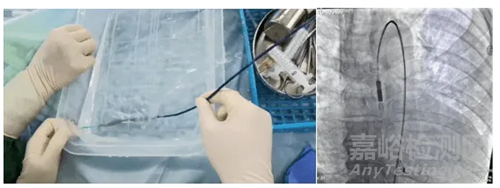

手術(shù)過程中,李虔楨教授在陳良萬教授的指導(dǎo)下經(jīng)股動脈穿刺建立導(dǎo)管泵通路,將pVAD 導(dǎo)管泵經(jīng)股動脈逆行置入患者左心室,在X光透視和食道超聲指導(dǎo)下導(dǎo)管泵置入到位,啟動導(dǎo)管泵穩(wěn)定運行十分鐘,復(fù)測食道超聲左室EF:35.7%,患者血壓提升,EF改善,血流動力學(xué)逐漸穩(wěn)定。

▲D-Omniheart試運行及植入影像

D-OmniHeart 經(jīng)皮心室輔助裝置是由董念國教授團(tuán)隊牽頭與上海心恒睿醫(yī)療科技有限公司聯(lián)合研發(fā),通過可植入體內(nèi)的微型電機(jī)直接驅(qū)動血泵運轉(zhuǎn),直接將血液從左心室經(jīng)由血泵導(dǎo)管提速增壓后進(jìn)入升主動脈,可提供最大4.0L/min輔助流量,以增加心排量、改善器官灌注效果、降低心臟負(fù)荷,給予臨床醫(yī)生更好地支持并且治療心血管疾病。

設(shè)備采用創(chuàng)新性高效泵結(jié)構(gòu),實現(xiàn)了流量精準(zhǔn)算法控制(2.5L/分鐘)灌注藥液功能,有效避免心內(nèi)血栓形成。2022年8月,D-Omniheart 經(jīng)皮心室輔助裝置完成了首例臨床植入,實現(xiàn)我國急性心源性休克患者微創(chuàng)介入心室內(nèi)輔助救治技術(shù)的突破。